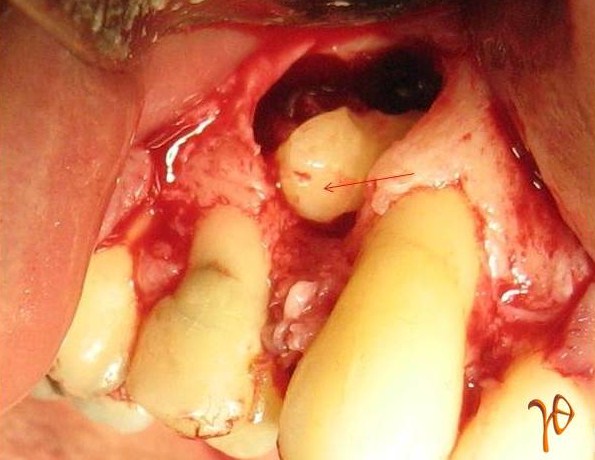

Εικ. 6 : Διεγχειρητική εικόνα του υπεράριθμου προγομφίου (βέλος). Ταυτόχρονη ακρορριζεκτομή του #13.

Εικ. 7 : Διεγχειρητική επιβεβαίωση της άκτινοδιαγνωστικής ένδειξης για απορρόφηση της ρίζας του #15 (βέλος).

Εικ. 10 : Διεγχειρητική εικόνα του υπεράριθμου προγομφίου της Περίπτωσης-2 (βέλος).

Eικ. 12 : Διεγχειρητική εικόνα του υπεράριθμου προγομφίου της Περίπτωσης-3(βέλος), ο οποίος διχοτομήθηκε για τις ανάγκες της εξαγωγής (ένθετη φωτογραφία).